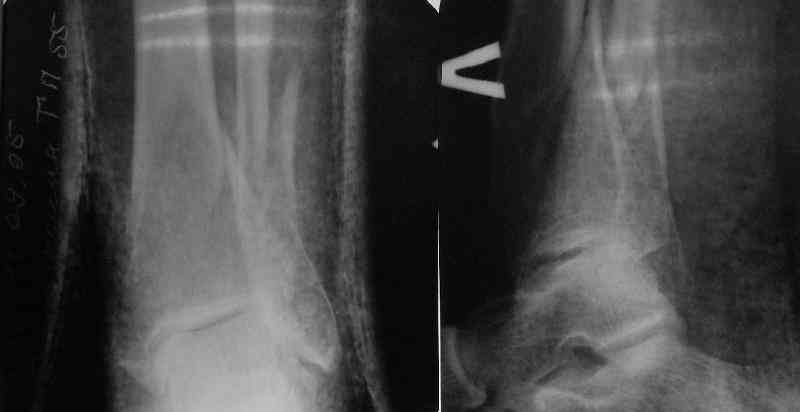

In delayed cases acute length restoration performed only in the tibia may leave the fibula shortened thus change the mortise. So it is reasonable to restore length of both bones simultaneously by distractor and fix the fibula not with open reduction and plating but just by a single perQ screw. Example attached.

A typical case is attached, also an image with intra-op reduction obtained by a small wire distractor, in the moment of insertion a Poller wire in AP direction. Fixation by a SIGN nail. Despite the fibula was not fixed healing was obtained with the unchanged alignment.

Very interesting application, but is the final position in a little distal varus with some fibula

At least both the ankle mortise and tibial alignment look acceptable, don't they?